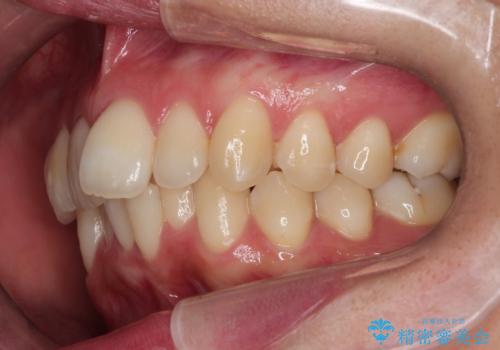

- 前歯のでこぼこが気になると来院されました。

奥歯の噛み合わせは綺麗に噛んでいたため、前歯の叢生(でこぼこ)を、短期間で治療完了するように計画しました。

奥歯の噛み合わせは整っていたため、前歯の並びを美しく修正することに専念できました。マウスピース矯正による治療で短期間で改善しました。